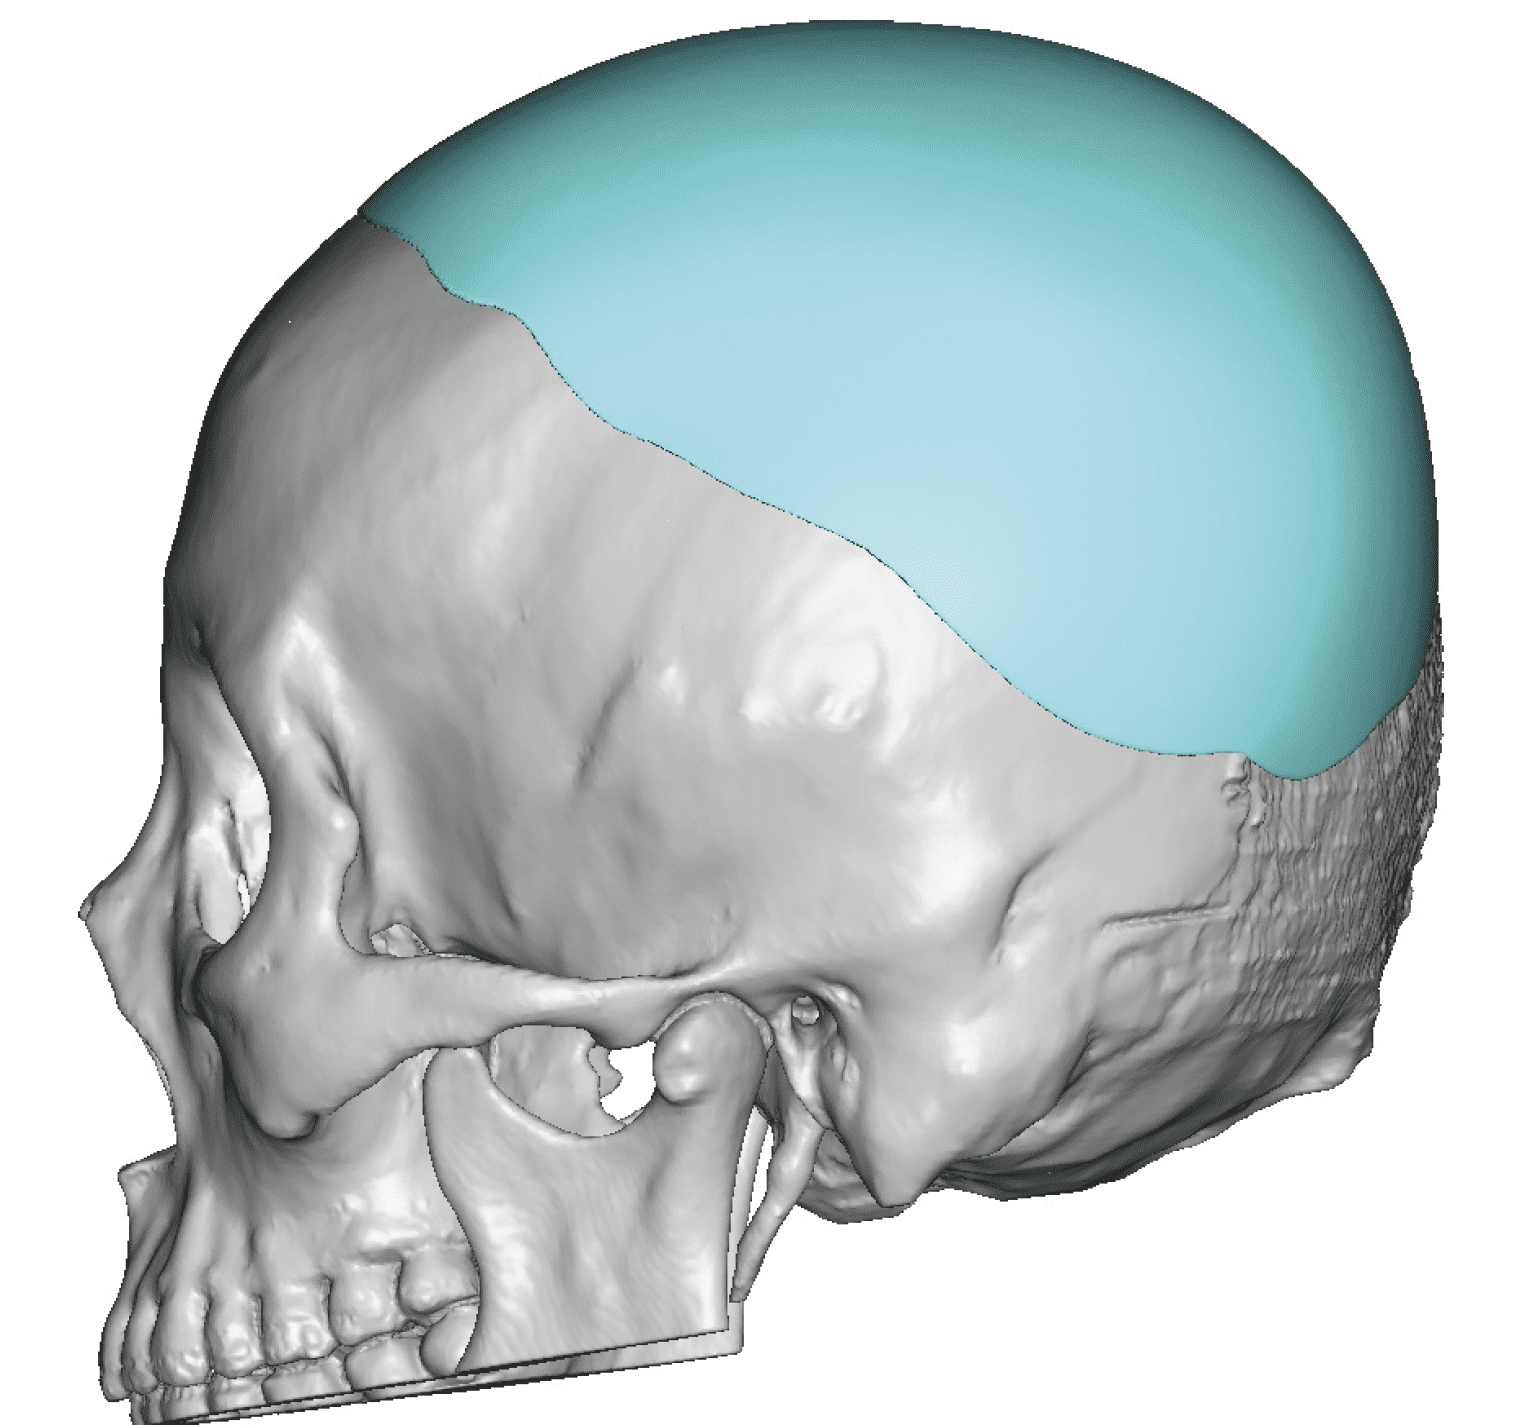

Patient 84

Desire for change of head shape from front view form an inverted V shape to a rounder and wider head shape.

Placement of custom extended forehead-temporal implants through incisions in the crease behind the ear. (he had a prior back of head skull implant which is green in the implant designs and which the head widening implants partially covered it)

Desire for change of head shape from front view form an inverted V shape to a rounder and wider head shape.

Placement of custom extended forehead-temporal implants through incisions in the crease behind the ear. (he had a prior back of head skull implant which is green in the implant designs and which the head widening implants partially covered it)